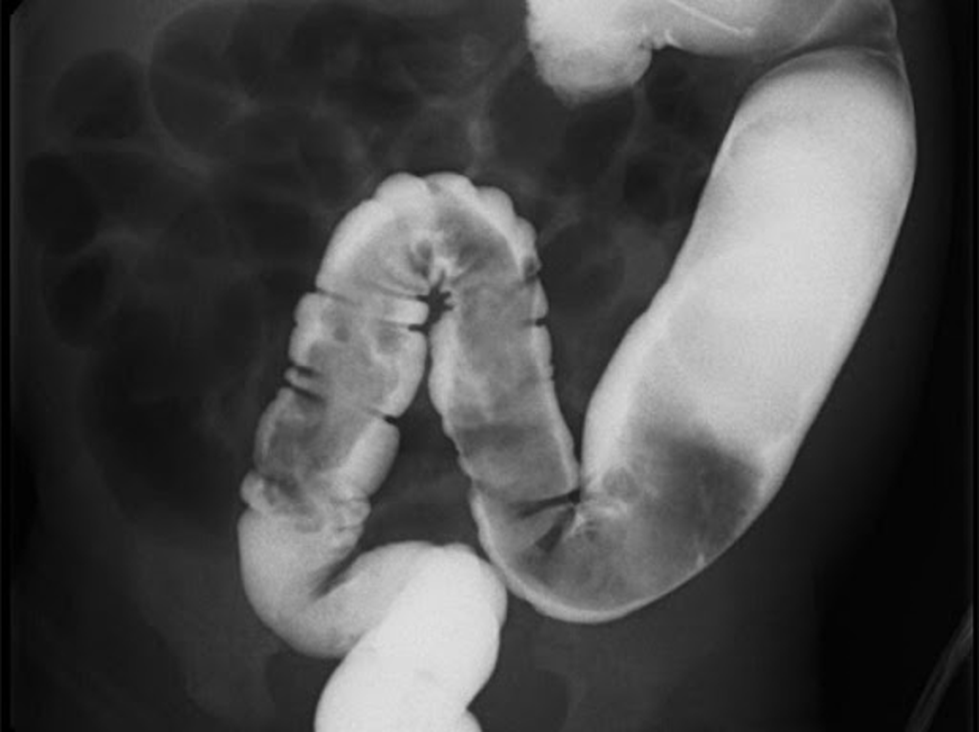

Thụt dung dịch barium

Có thể cho thấy sự thay đổi đường kính giữa đoạn đại tràng bình thường và đoạn bị giãn (không thấy các hạch thần kinh ở đoạn bất thường).

Trước khi dùng barium, không dùng thuốc xổ để làm sạch đại tràng vì có thể làm giãn đoạn bất thường và ảnh hưởng kết quả chẩn đoán. Bởi vì không có biểu hiện đặc trưng trong giai đoạn sơ sinh, nên chụp X-quang sau khi thụt 24 giờ; nếu vẫn còn barium trong đại tràng thì nghi ngờ bệnh nhân mắc bệnh.